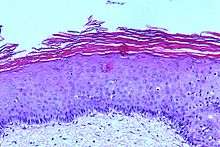

Histologic appearance

Leukoplakia has a wide range of possible histologic appearances. The degree of hyperkeratosis, epithelial thickness (acanthosis/atrophy), dysplasia and inflammatory cell infiltration in the underlying lamina propria are variable.[7] In mucous membranes, hyperkeratosis can be defined as "an increase in the thickness of the keratin layer of the epithelium, or the presence of such a layer in a site where none would normally be expected."[22] In leukoplakia, the hyperkeratosis varies in thickness, and may be either ortho- or para-keratosis, (depending upon whether cell nuclei are lost or retained in the superficial layers respectively), or a mixture of both in different areas of the lesion.[7][28]

The epithelium may show hypertrophy (e.g. acanthosis) or atrophy. Red areas within leukoplakia represent atrophic or immature epithelium which has lost the ability to keratinize.[1] The transition between the lesion and normal surrounding mucosa may be well demarcated, or poorly defined. Melanin, a pigment naturally produced in oral mucosa, can leak from cells and give a grey color to some leukoplakia lesions.[7]

Hyperkeratosis and altered epithelial thickness may be the only histologic features of a leukoplakia lesion, but some show dysplasia. The word dyspalsia generally means "abnormal growth", and specifically in the context of oral red or white lesions refers to microscopic changes ("cellular atypia") in the mucosa that indicate a risk of malignant transformation.[3] When dysplasia is present, there is generally an inflammatory cell infiltration in the lamina propria.[28] The following are commonly cited as being possible features of epithelial dysplasia in leukoplakia specimens:[3][7]